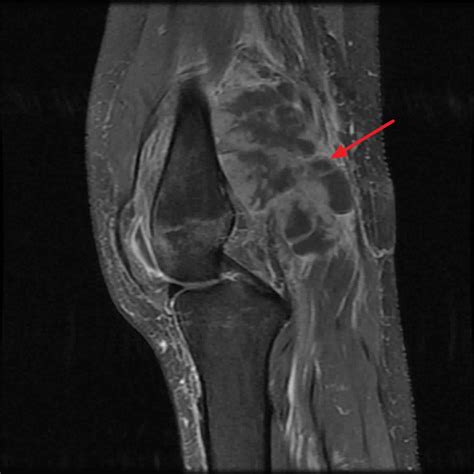

• Tumor Site: The location of the primary tumor matters. Tumors located in the pelvis or certain areas of the spine are often more challenging to treat effectively compared to those located in the arms or legs (extremities).

• Response to Treatment: How well the tumor shrinks during initial (neoadjuvant) chemotherapy is a strong indicator of the long-term prognosis.

The outlook for Ewing sarcoma has seen meaningful improvement over the past few decades, largely due to better risk stratification and advancements in imaging and molecular biology. Researchers are currently exploring how genomic profiling of the tumor can identify weaknesses that can be targeted with precision medicines, reducing the reliance on toxic, broad-spectrum chemotherapies.